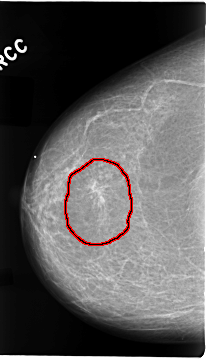

C_0073_1.RIGHT_CC

FILE: C_0073_1.RIGHT_CC.OVERLAY

TOTAL_ABNORMALITIES 1

ABNORMALITY 1

LESION_TYPE MASS SHAPE ARCHITECTURAL_DISTORTION MARGINS SPICULATED

ASSESSMENT 4

SUBTLETY 5

PATHOLOGY MALIGNANT

TOTAL_OUTLINES 1

BOUNDARY